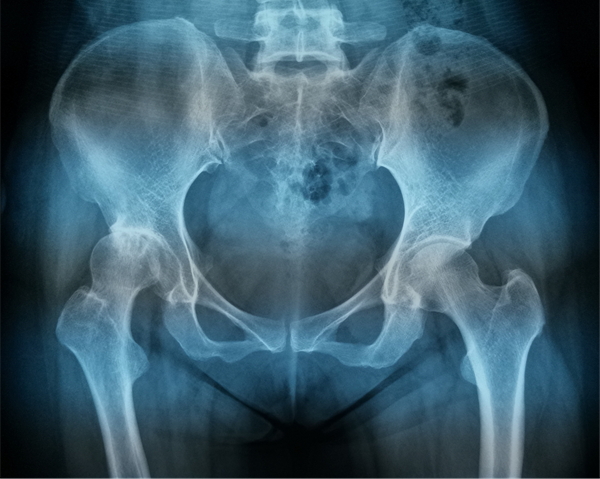

为了解除母亲的病痛,刘阿姨的女儿带着她来到哈医大一院,找到了毕郑刚和耿硕团队。经过细致的问诊、查体和相关影像学检查,毕郑刚和耿硕发现刘阿姨患有髋关节发育不良,从而导致了髋关节的重度骨性关节炎,这种情况可以通过全髋关节置换手术来治疗。

骨科关节置换手术,术前精准手术方案的制定是手术成功与否的关键。手术前,耿硕根据患者术前三维CT扫描数据,进行三维术前规划,精确测量患者相关参数,计算适合患者假体型号及测试假体安放位置,实现个性化定制手术方案,经过术前规划,刘阿姨右侧髋关节应当采用54mm G7髋臼杯,11号ML taper股骨柄,这套方案适合刘阿姨的生理解剖,使术后功能更加良好。